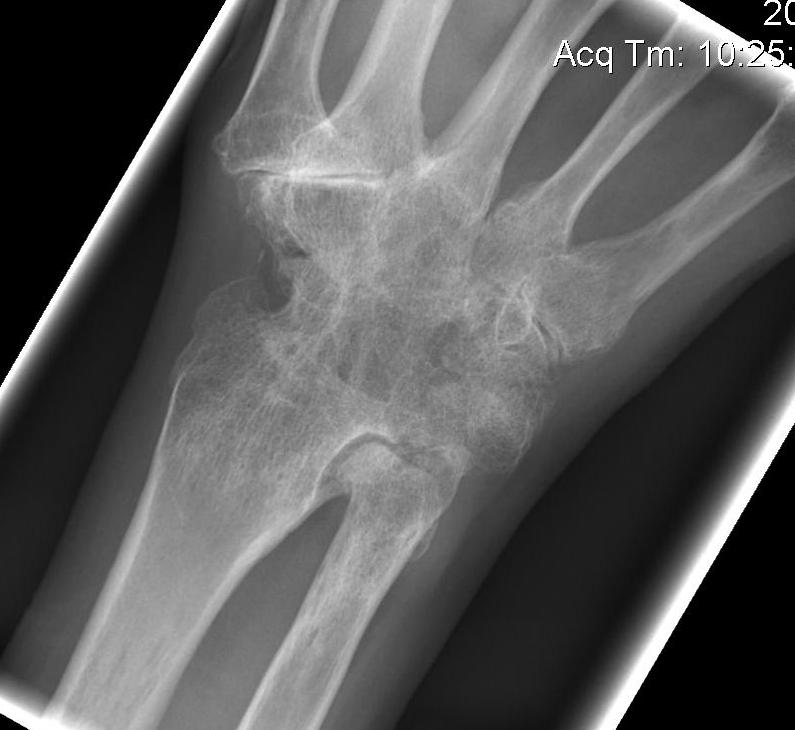

Xray